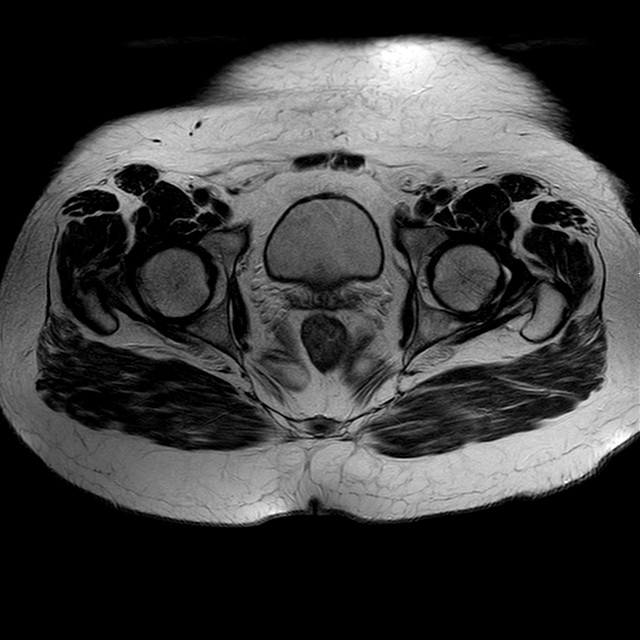

Esami: RMN BACINO

eT2w TSE

Evidenti e simmetriche alterazioni osteofitosiche in regione coxo femorale con riduzione delle rime articolari. Degenerazione completa del cercine glenoideo. Non attuali segni di versamento articolare. Non segni di edema osseo che escludono attuale algodistrofia od osteonecrosi. Lieve e simmetrica riduzione del trofismo della muscolatura glutea.